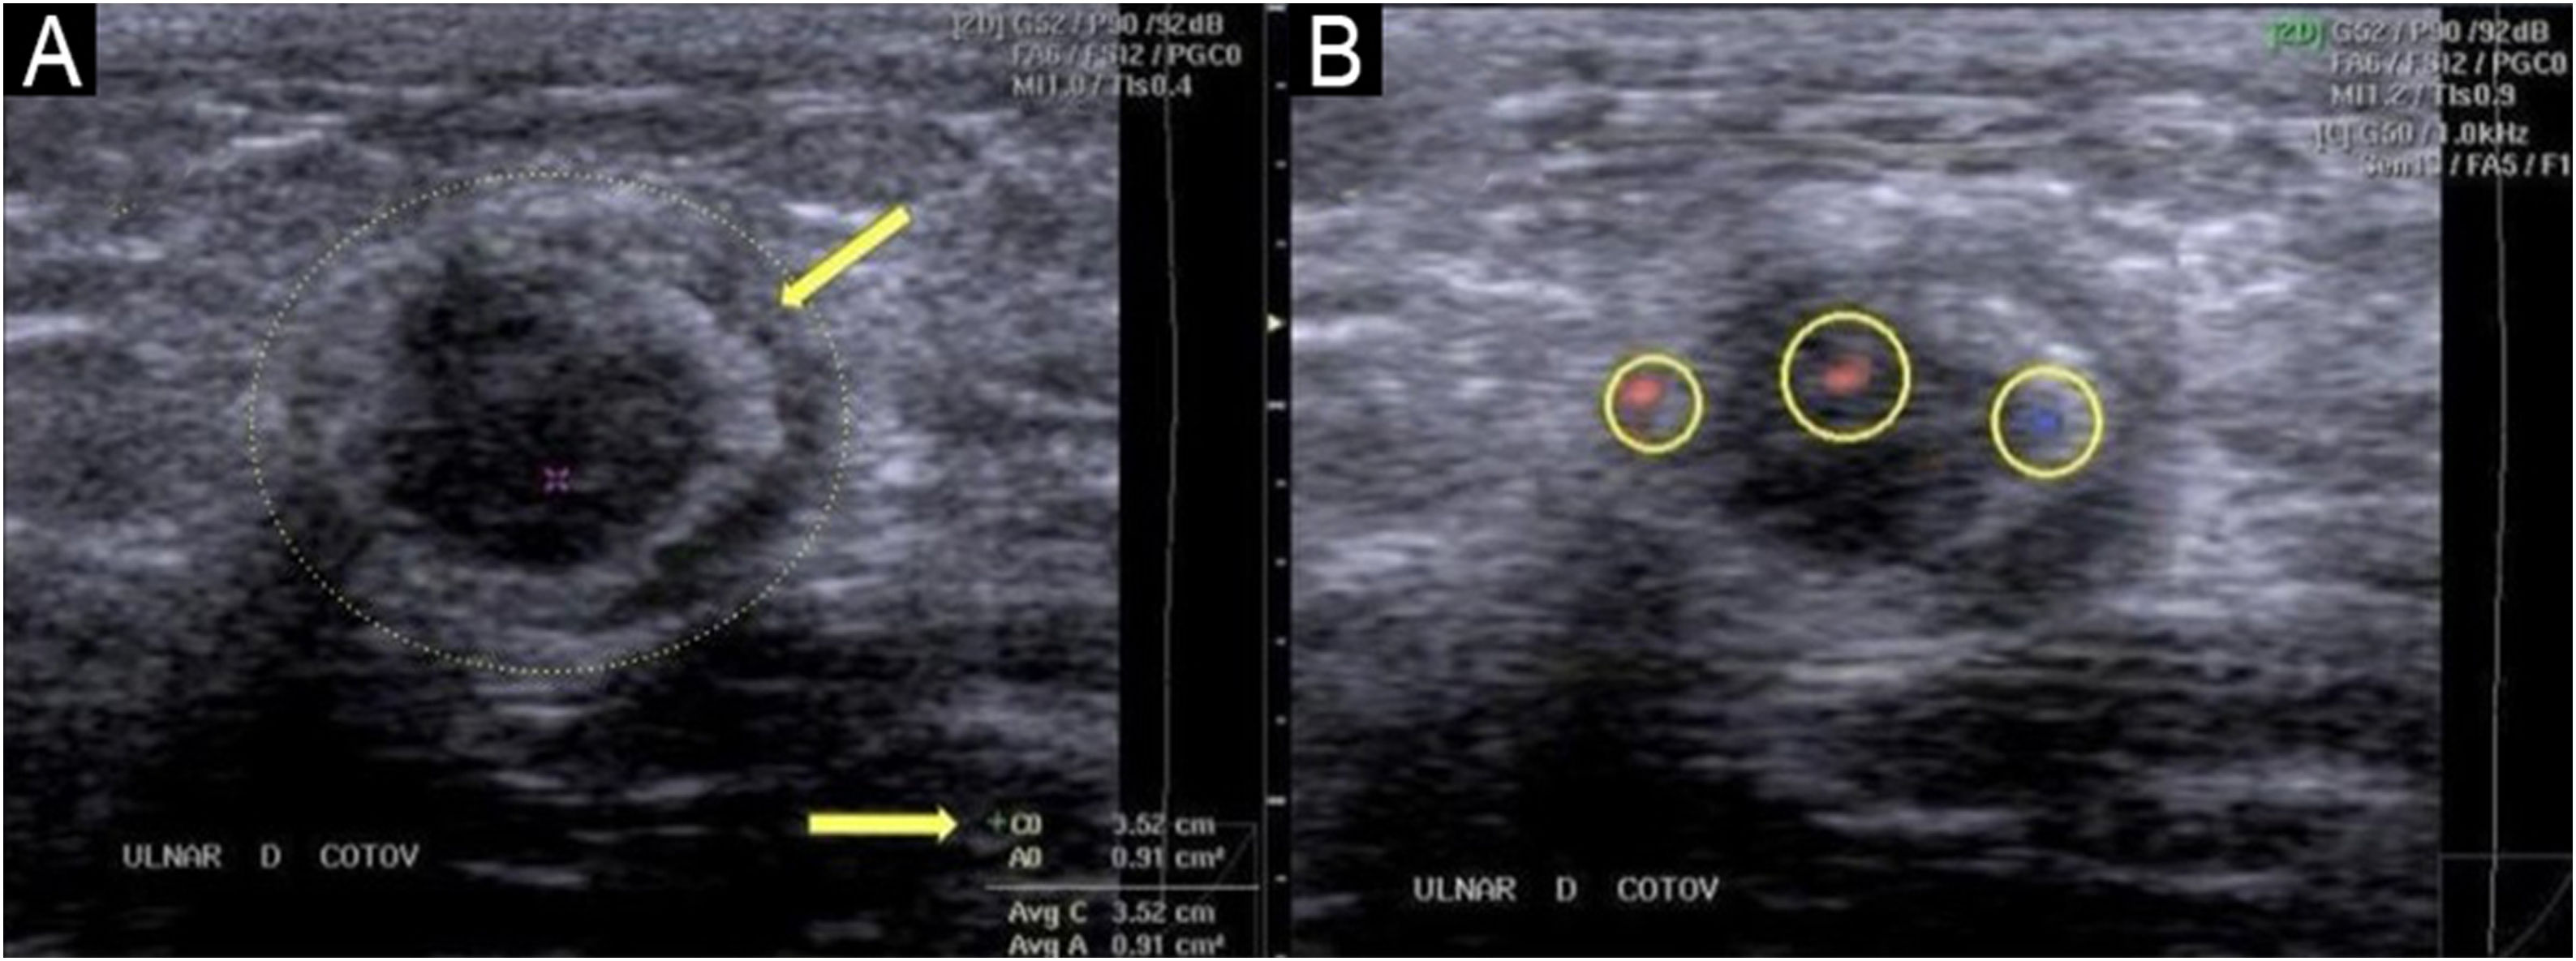

Ultrasonography of the ulnar nerve (transverse plane at the elbow).

(A) B-mode imaging reveals marked thickening with a perimeter of 3.52 cm and an area of approximately 0.91 cm2 (≈91 mm2); for reference, normal is approximately 0.10 cm2 (≈10 mm2). Note epineurial thickening and a crescent-shaped hyperechoic halo (arrow). (B) Color Doppler at the same level shows three foci of peri-/intraneural flow (circles 1–3) within the Doppler box, consistent with inflammatory neuritis.

Ultrasonography offers significant advantages over clinical palpation for detecting nerve thickening. The kappa coefficient, which measures agreement between methods [ranging from 0 (no agreement) to 1 (perfect agreement)], is only 0.30 between palpation and ultrasound, indicating low concordance. This shows that many nerves found to be thickened on ultrasound are not detected by palpation, and conversely, nerves considered thickened on palpation may measure normal on ultrasound.82